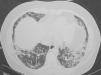

Mujer de 37 años, que ingresó en nuestro servicio por presentar disnea. Era exfumadora de 5 años-paquete y no presentaba ningún otro antecedente patológico de interés. Trabajaba de ama de casa y realizaba alguna tarea en agricultura (cerezos y almendros), pero sin contacto con insecticidas. No presentaba ningún antecedente familiar de interés ni seguía ningún tipo de medicación habitual. Refería contacto con perros, gatos y palomos. Un mes antes del ingreso había comenzado con disnea, que fue progresiva hasta convertirse en disnea de mínimos esfuerzos, sin ningún otro síntoma. En la exploración física destacó la presencia de crepitantes tipo velcro en el tercio inferior de ambos campos pulmonares; el resto fue normal. En la radiografía de tórax se observó un patrón intersticial de predominio en campos inferiores y distribución periférica. La analítica sanguínea mostró una velocidad de sedimentación globular de 37 mm/h; el resto de los parámetros fue normal, incluidos gasometría arterial, enzima conversiva de la angiotensina, hormonas tiroideas, anticuerpo antinuclear y factor reumatoide. Las serologías para los virus de la inmunodeficiencia humana y de la hepatitis C y B fueron negativas, al igual que las precipitinas para antígeno de paloma. La exploración funcional respiratoria mostró los siguientes datos: capacidad vital forzada (FVC) de 1.810 ml (47%), volumen espiratorio forzado en el primer segundo (FEV1) de 1.740 ml, FEV1%/FVC del 116% del teórico, capacidad pulmonar total (TLC) de 2.990 ml (58%), volumen residual (RV) de 930 ml, RV%/TLC del 97% del teórico, capacidad de difusión de monóxido de carbono del 34% del teórico y capacidad de difusión de monóxido de carbono ajustada al volumen alveolar del 70% del teórico. Se realizó una tomografía computarizada de alta resolución (fig. 1), que mostró áreas de vidrio deslustrado, parcheadas con engrosamiento de los septos interlobulillares, y áreas de condensación focal irregulares. Se realizó asimismo una fibrobroncoscopia con lavado broncoalveolar en el lóbulo medio y tomas de biopsia transbronquial a través del bronquio segmentario 8 derecho. En el lavado broncoalveolar se encontraron 400 células/μl (un 90% macrófagos, un 6% linfocitos, un 4% polimorfonucleares y un 0% eosinófilos; subpoblaciones de linfocitos: un 14% CD4 y un 79% CD8). El cultivo para gérmenes habituales y el cultivo de Löwenstein fueron negativos, y la citología no mostró evidencia de malignidad. La biopsia mostró una alteración de la arquitectura por fibrosis de densidad celular variable y un leve componente plasmocítico acompañante, sin observarse focos fibroblásticos. Tras la realización de estas pruebas se descartó la presencia de fibrosis pulmonar idiopática, por lo que se decidió iniciar tratamiento con prednisona a dosis de 2 mg/kg de peso y realizar una biopsia pulmonar por videotoracoscopia. La pieza pulmonar mostró una metaplasia peribronquiolar con leve fibrosis e infiltrado inflamatorio mononuclear, con arquitectura pulmonar conservada, sin granulomas, fibrosis, inflamación alveolointersticial ni cuerpos extraños (fig. 2). El diagnóstico final fue de neumonía intersticial bronquiolocéntrica idiopática.

Fig. 1. Tomografía computarizada de alta resolución, donde se observa la presencia de áreas de vidrio deslustrado, parcheadas con engrosamiento de los septos interlobulillares, y áreas irregulares de condensación focal.